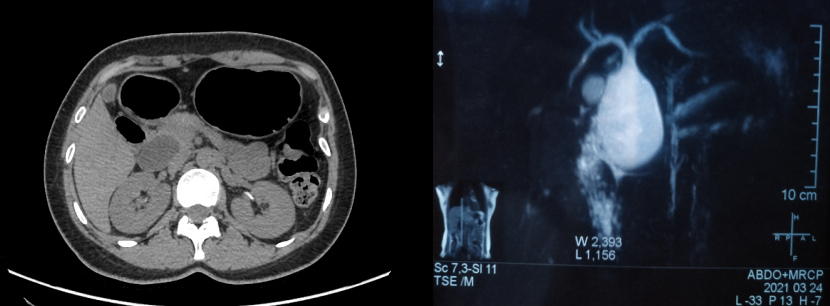

2021年3月,来自山西朔州的年轻女患者,反复出现上腹部疼痛20余年,近一个月腹痛加重,于当地医院诊断为先天性胆管扩张症Ⅰ型,建议做腹腔镜微创手术,但由于条件所限不能完成。患者通过多方咨询,慕名来到我院普外一科(肝胆胰脾),请求张俊晶副院长为她做手术。

先天性胆管扩张症发病率较低,亚裔发病较其他人种稍高。随着年龄增加扩张的胆管恶变风险逐年增加。普外一科于2021年4月2日在全麻下为该患者行全腹腔镜胆管病损切除胆管空肠吻合内引流术,手术由张俊晶副院长主刀,此项手术为我院首例,在内蒙古自治区外科领域达到领先水平。

手术首先分离肝外胆管的囊性扩张,扩张的胆管深入胰腺段很深,切断扩张的胆管及胆囊,将空肠肠袢与预留胆管进行缝合,再将空肠进行肠肠侧吻合,手术时间230分钟,出血量约50ml。